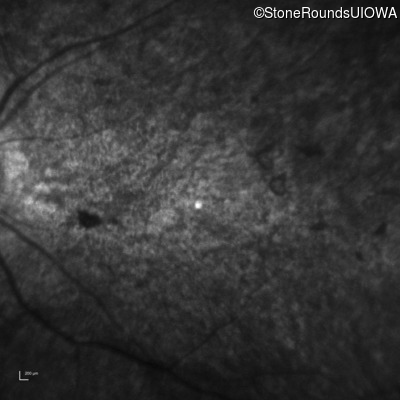

Infrared Fundus Photograph - Right - 20/400 sc

Exemplar

Infrared Fundus Photograph - Left - 20/250 sc